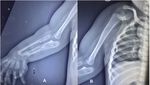

Seorang anak laki-laki berusia dua tahun di India, terlahir dengan kondisi langka anomali kongenital (congenital anomalies) yang membuat dirinya mengalami tiga lengan bawah dan duplikasi jari. Kasusnya ini diterbitkan dalam jurnal PlumX Metrics pada 2024, dengan judul ‘Congenital three-bone forearm – A rare disorder’.

Selain itu, rontgen tangan menunjukkan duplikasi tipe III pada jari tengah, duplikasi tipe V pada jari manis, jari kelingking yang mengalami deviasi ulnar, serta pergelangan tangan dengan tiga tulang. Sementara itu, anggota gerak atas kiri, wajah, tulang belakang, panggul, dan ekstremitas bawah tampak normal. Pasien tidak mengalami obesitas, dan hasil parameter darah berada dalam batas normal.Foto: jurnal PlumX Metrics

Berdasarkan hasil pemeriksaan, terlihat adanya pengecilan otot yang nyata di sekitar bahu dan skapula, disertai tidak adanya gerakan aktif pada abduksi, fleksi, maupun rotasi bahu. Siku dalam posisi fleksi 30 derajat tanpa kemampuan melakukan supinasi maupun pronasi. Lengan bawah dan pergelangan tangan tampak melebar.